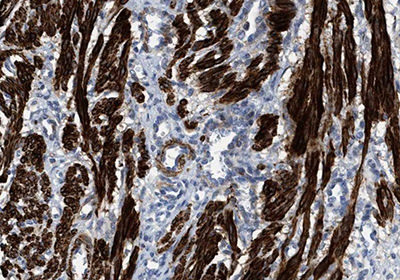

A myocyte is the functional cell type of muscle tissue. There are three different types of myocytes with distinct properties and include smooth, cardiac and skeletal muscle cells. Smooth muscle cells (SMC) build up as involuntarily controlled, non-striated muscles in the walls of visceral tissues and blood vessels. The master regulation of smooth muscle gene expression is mediated by myocardin. Cardiomyocytes, or heart muscle cells, are involuntarily controlled, striated cells confined to the heart. Cardiomyocytes are, among other factors, regulated by GATA4 and myocardin. Skeletal muscle cells are striated muscle cells under voluntary control and are attached to the skeleton by tendons. MyoD1 is a key regulator of skeletal (striatal) muscle cell differentiation. Figures 5A-C show immunostainings exemplifying specific antibody markers for each type of muscle cell.

Figure 5A.Immunohistochemical staining of smooth muscle cell (SMC) showing high expression of Transgelin using Anti-TAGLN polyclonal antibody (HPA019467).